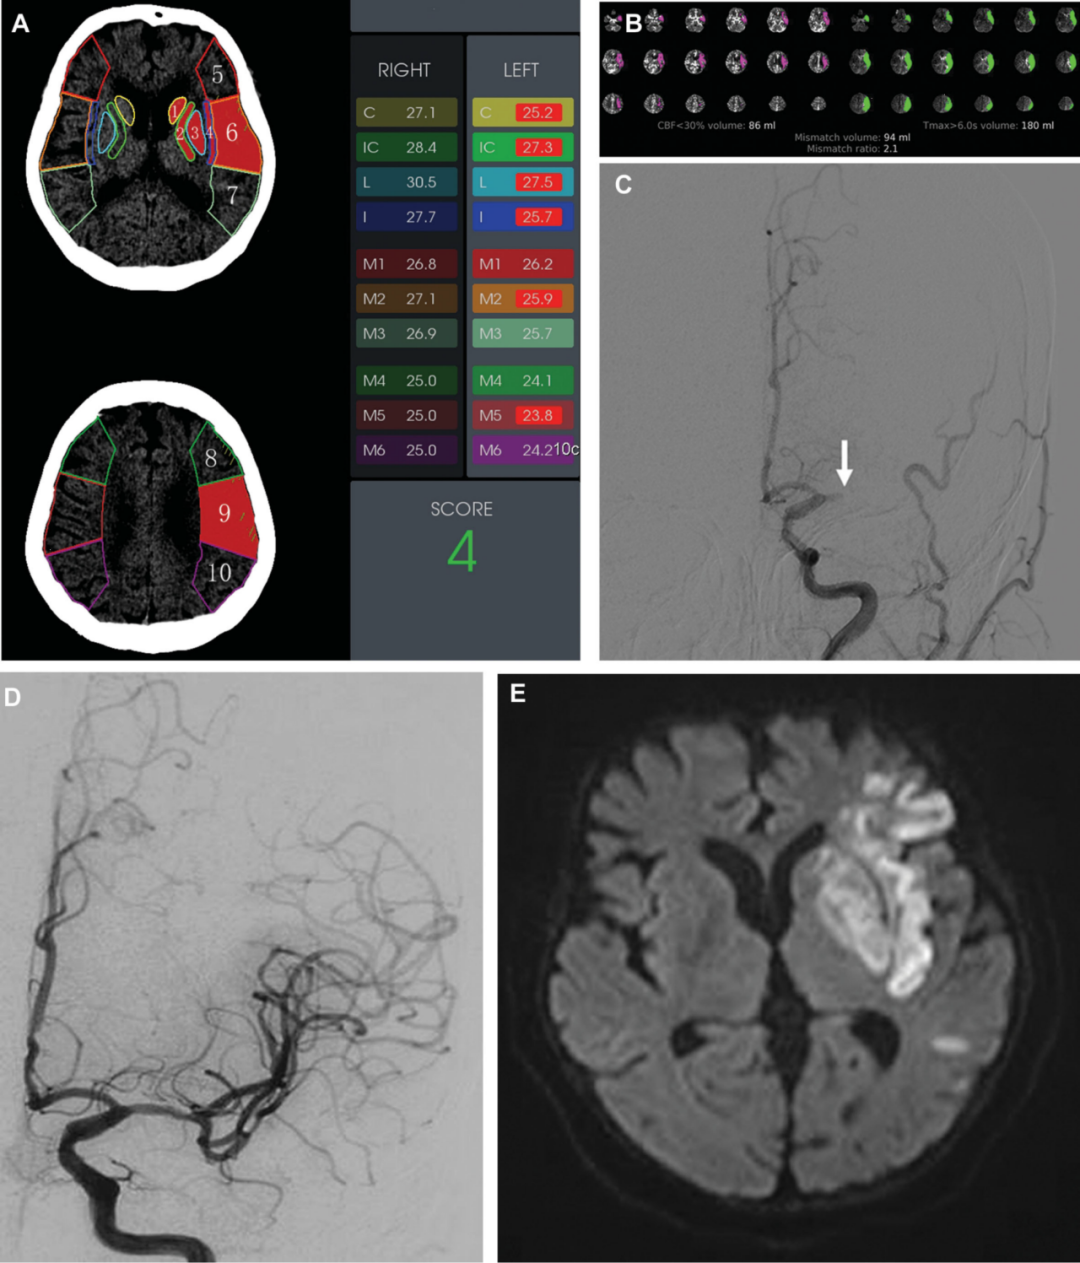

废墟中寻找生命的讯息晚时间窗超低aspects评分大面积脑梗死急诊取栓

aspects评分:将mca供血区分为10区,平扫ct低密度灶或强化ct/cta无